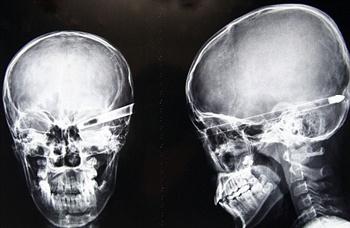

این دانش آموز چینی در هنگام تمرین تیر و کمان، تیری به چشمش فرو رفت و به طور معجزه آسایی نجات پیدا کرد.

تیر پرتاب شده توسط یان شین، دانش آموز 13 ساله در استان شرقی جین تای چین به چشم لیو چئونگ 11 ساله اصابت کرد. برای آنکه بتوانند لیو را وارد دستگاه MR کنند تیر را شکستند. معجزه ای که رخ داده بود این بود که تیر نه به عصب های چشم این نوجوان اصابت کرده بود و نه آسیبی به مغز رسانده بود. معجزه ای که به گفته پزشکان در هر چند میلیون مورد، یک بار اتفاق می افتد.

پزشکان بعد از یک عمل جراحی چهار ساعته توانستند با موفقیت تیر را از چشم پسرک چینی در بیاورند.